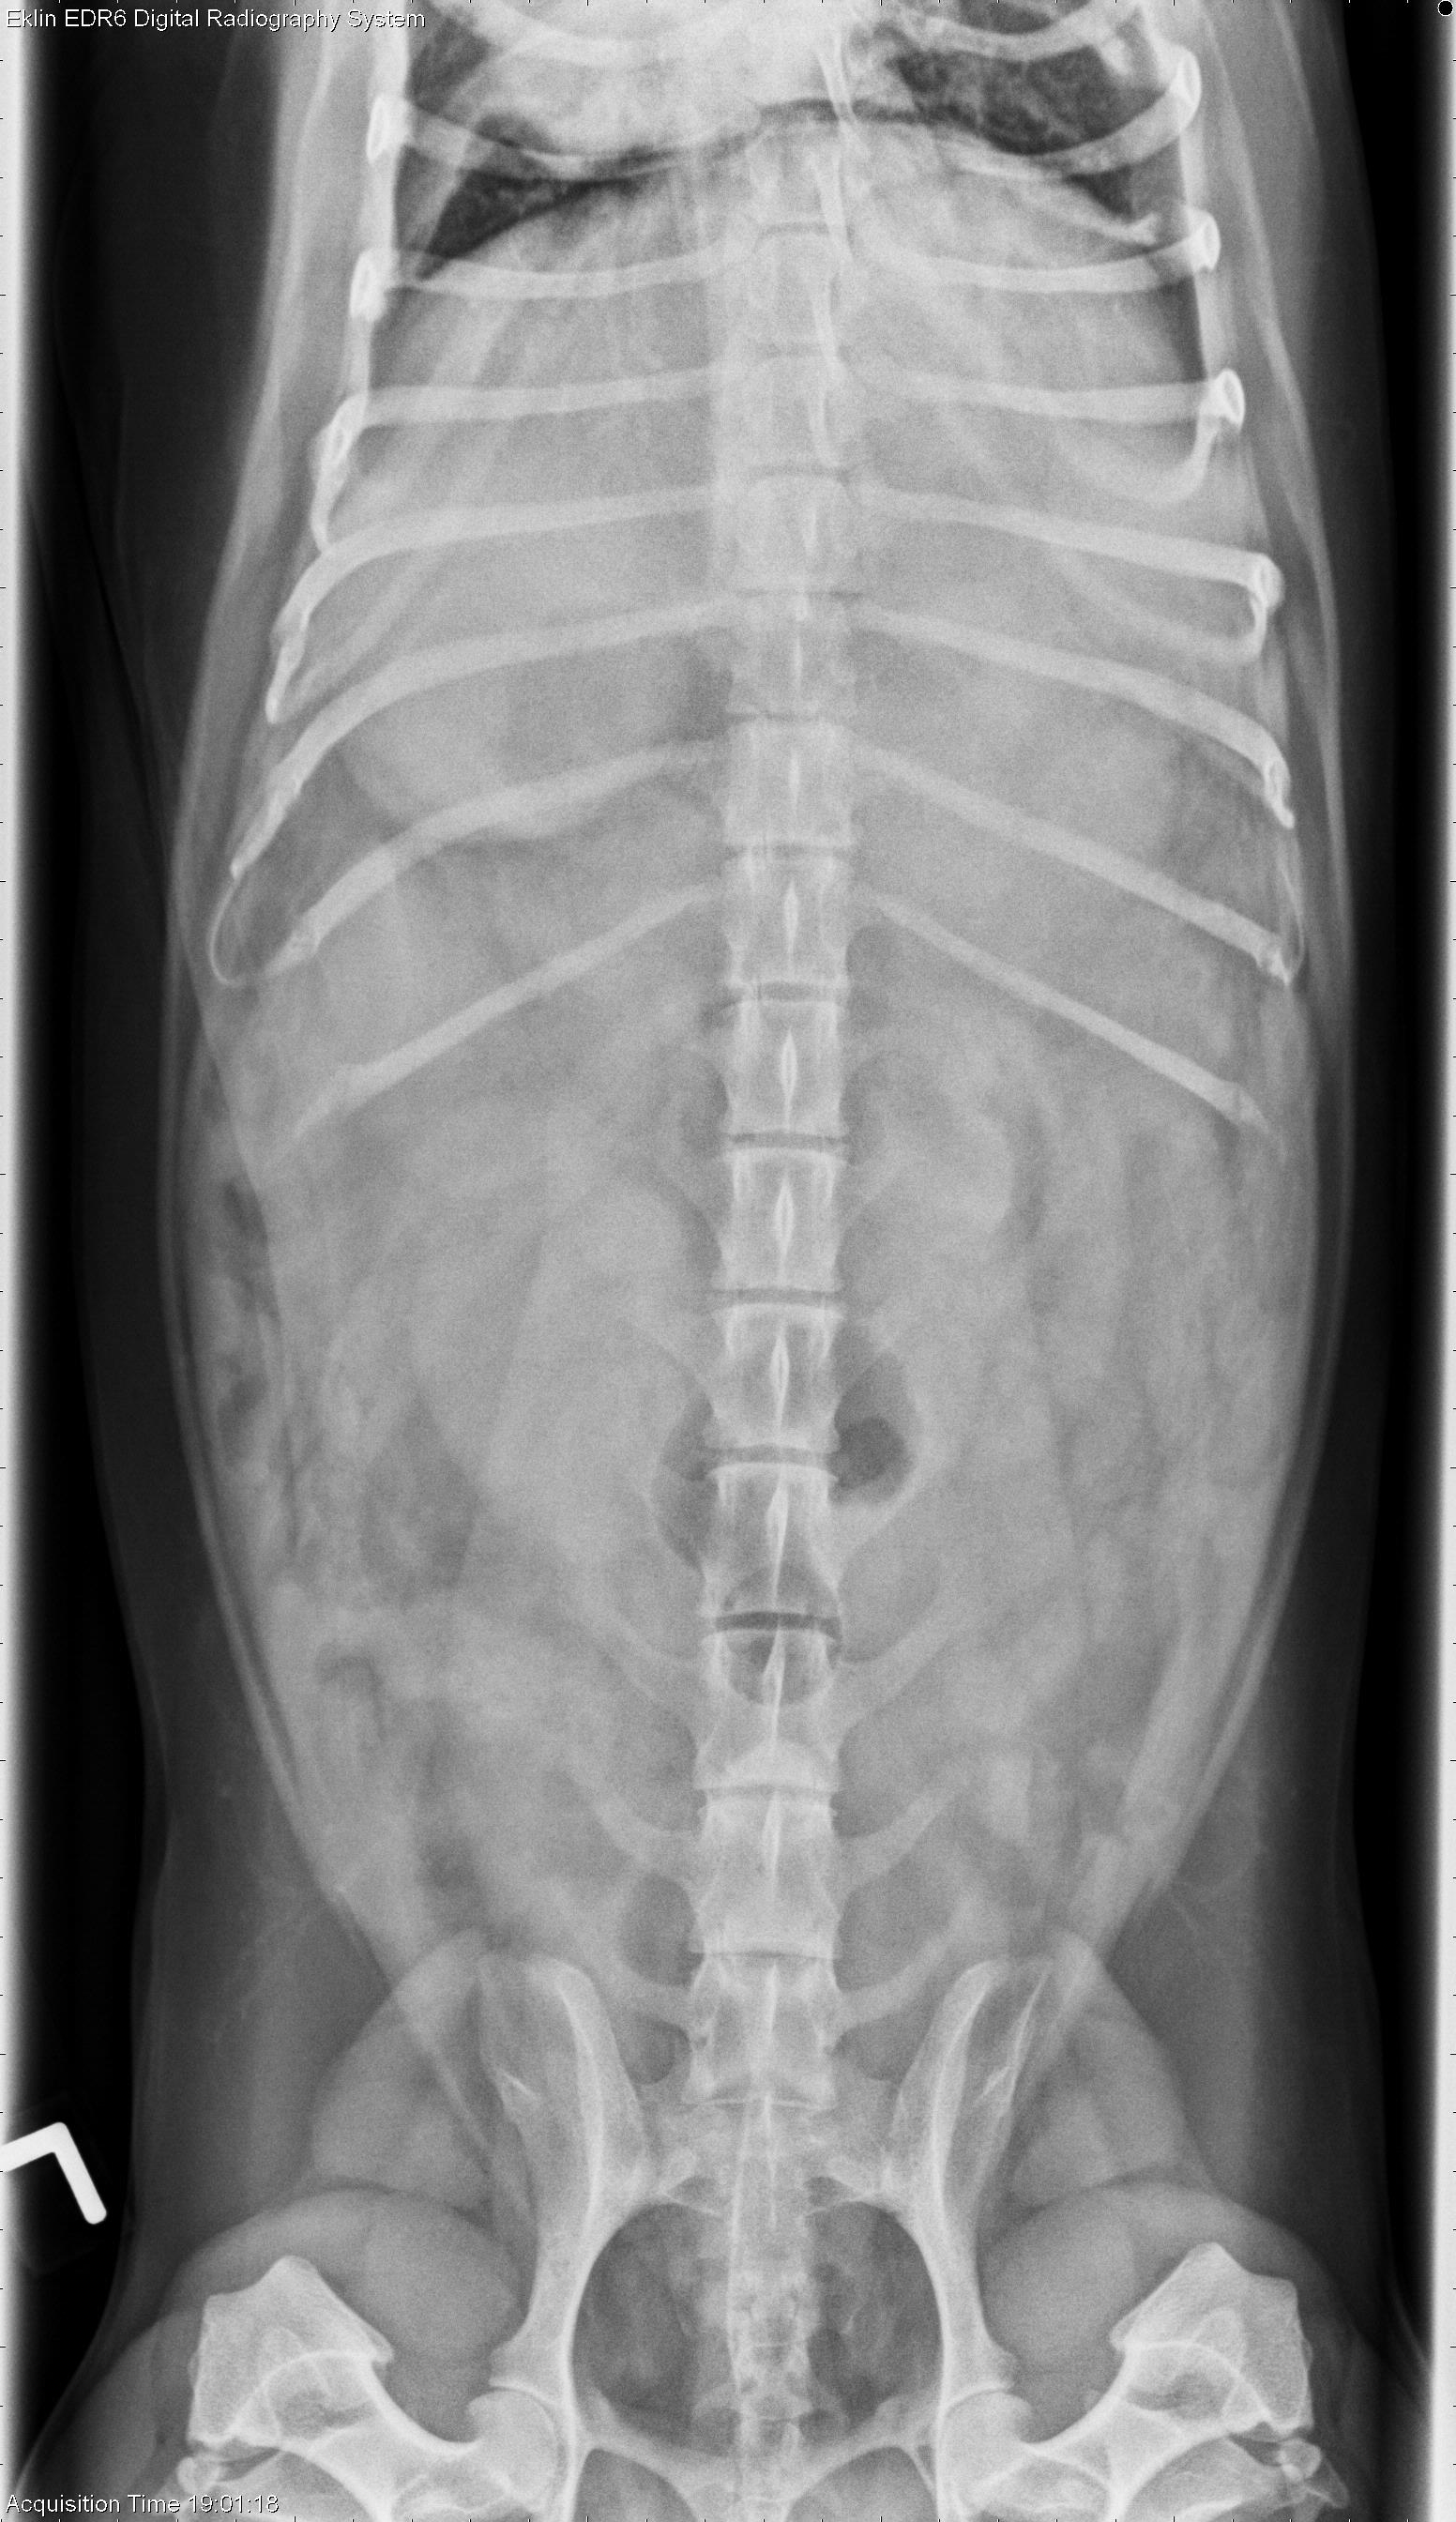

2 year old Dachshund

This week’s case is a 2-year-old male neutered Dachshund with 1-day history of vomiting and lethargy. Peritoneal detail is a clue as to where the lesion is in this case. What is your interpretation?

Abdomen: There is mottled poor detail in the cranial abdomen. There is a mass effect caudal to the stomach on the right and left lateral projections. On the ventrodorsal projection, the poor detail is most apparent in the left cranial abdomen with a mass effect. The kidneys and urinary bladder are normal. The cecum is gas filled. No other abnormalities are identified.

• Mass effect and poor detail may be due to pancreatitis or mass originating from the mesenteric lymph nodes.

• Recommend abdominal ultrasound for evaluation of the pancreas

• Severe necrotizing pancreatitis diagnosed at ultrasound and at surgery.